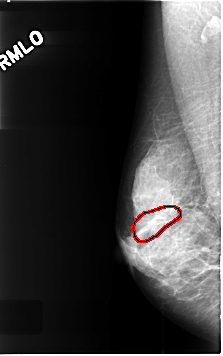

C_0461_1.RIGHT_MLO

RIGHT_MLO LINES 4616 PIXELS_PER_LINE 2888 BITS_PER_PIXEL 12 RESOLUTION 50 OVERLAY

FILE: C_0461_1.RIGHT_MLO.OVERLAY

TOTAL_ABNORMALITIES 1

ABNORMALITY 1

LESION_TYPE MASS SHAPE ARCHITECTURAL_DISTORTION MARGINS N/A

ASSESSMENT 3

SUBTLETY 4

PATHOLOGY BENIGN_WITHOUT_CALLBACK

TOTAL_OUTLINES 1

BOUNDARY